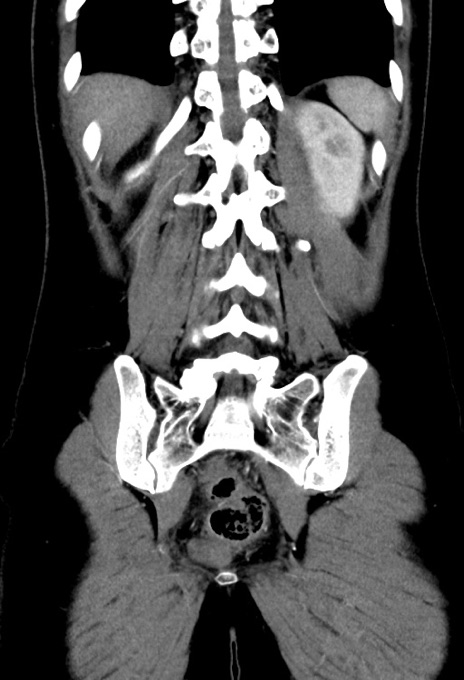

症例17(冠状断像)

【症例】20歳代女性

【主訴】嘔吐、下腹部痛

【現病歴】昨日夕食後に嘔吐し下腹部痛が出現。本日になっても嘔吐持続し改善しないため来院。

【身体所見】意識清明、BT 37.2℃、BP 108/67mmHg、腹部:平坦、やや硬、下腹部正中から右にかけて圧痛あり、反跳痛軽度あり、tapping pain(+)。

【データ】WBC 13600、CRP 14.94